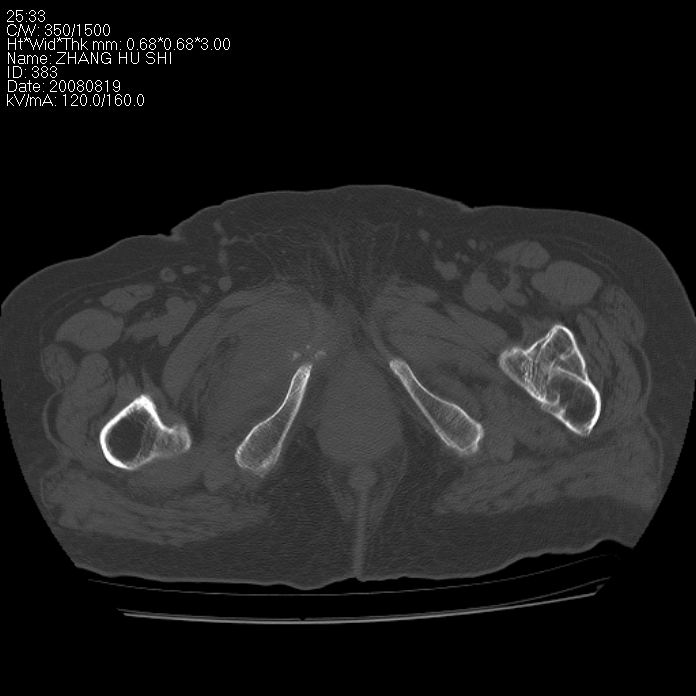

标题: CT15287:女 93岁 右髋关节疼痛 原左侧粗隆间骨折 CT发现右耻 [打印本页]

标题: CT15287:女 93岁 右髋关节疼痛 原左侧粗隆间骨折 CT发现右耻

支持转移

支持转移并周围软组织侵犯右闭孔内肌侵犯,但tb不能完全除外。